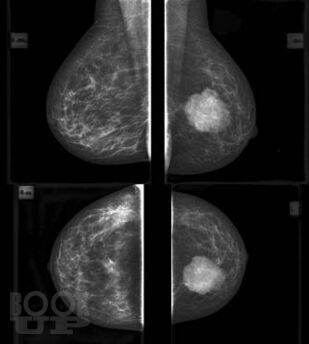

В основу книги положены материалы собственных исследований авторов и практический опыт использования комплекса новейших методик ультразвукового исследования в диагностике рака молочной железы, изучении состояния регионарных зон лимфоотока. Цель книги – помочь практикующим специалистам ультразвуковой, лучевой диагностики, маммологам, гинекологам, врачам общей практики систематизировать знания по эффективному использованию в своей практике новейших технологий ультразвукового исследования, обучить основам комплексной первичной и дифференциальной диагностики патологии молочных желез. Издание хорошо иллюстрировано, содержит большое количество рисунков, эхограмм.